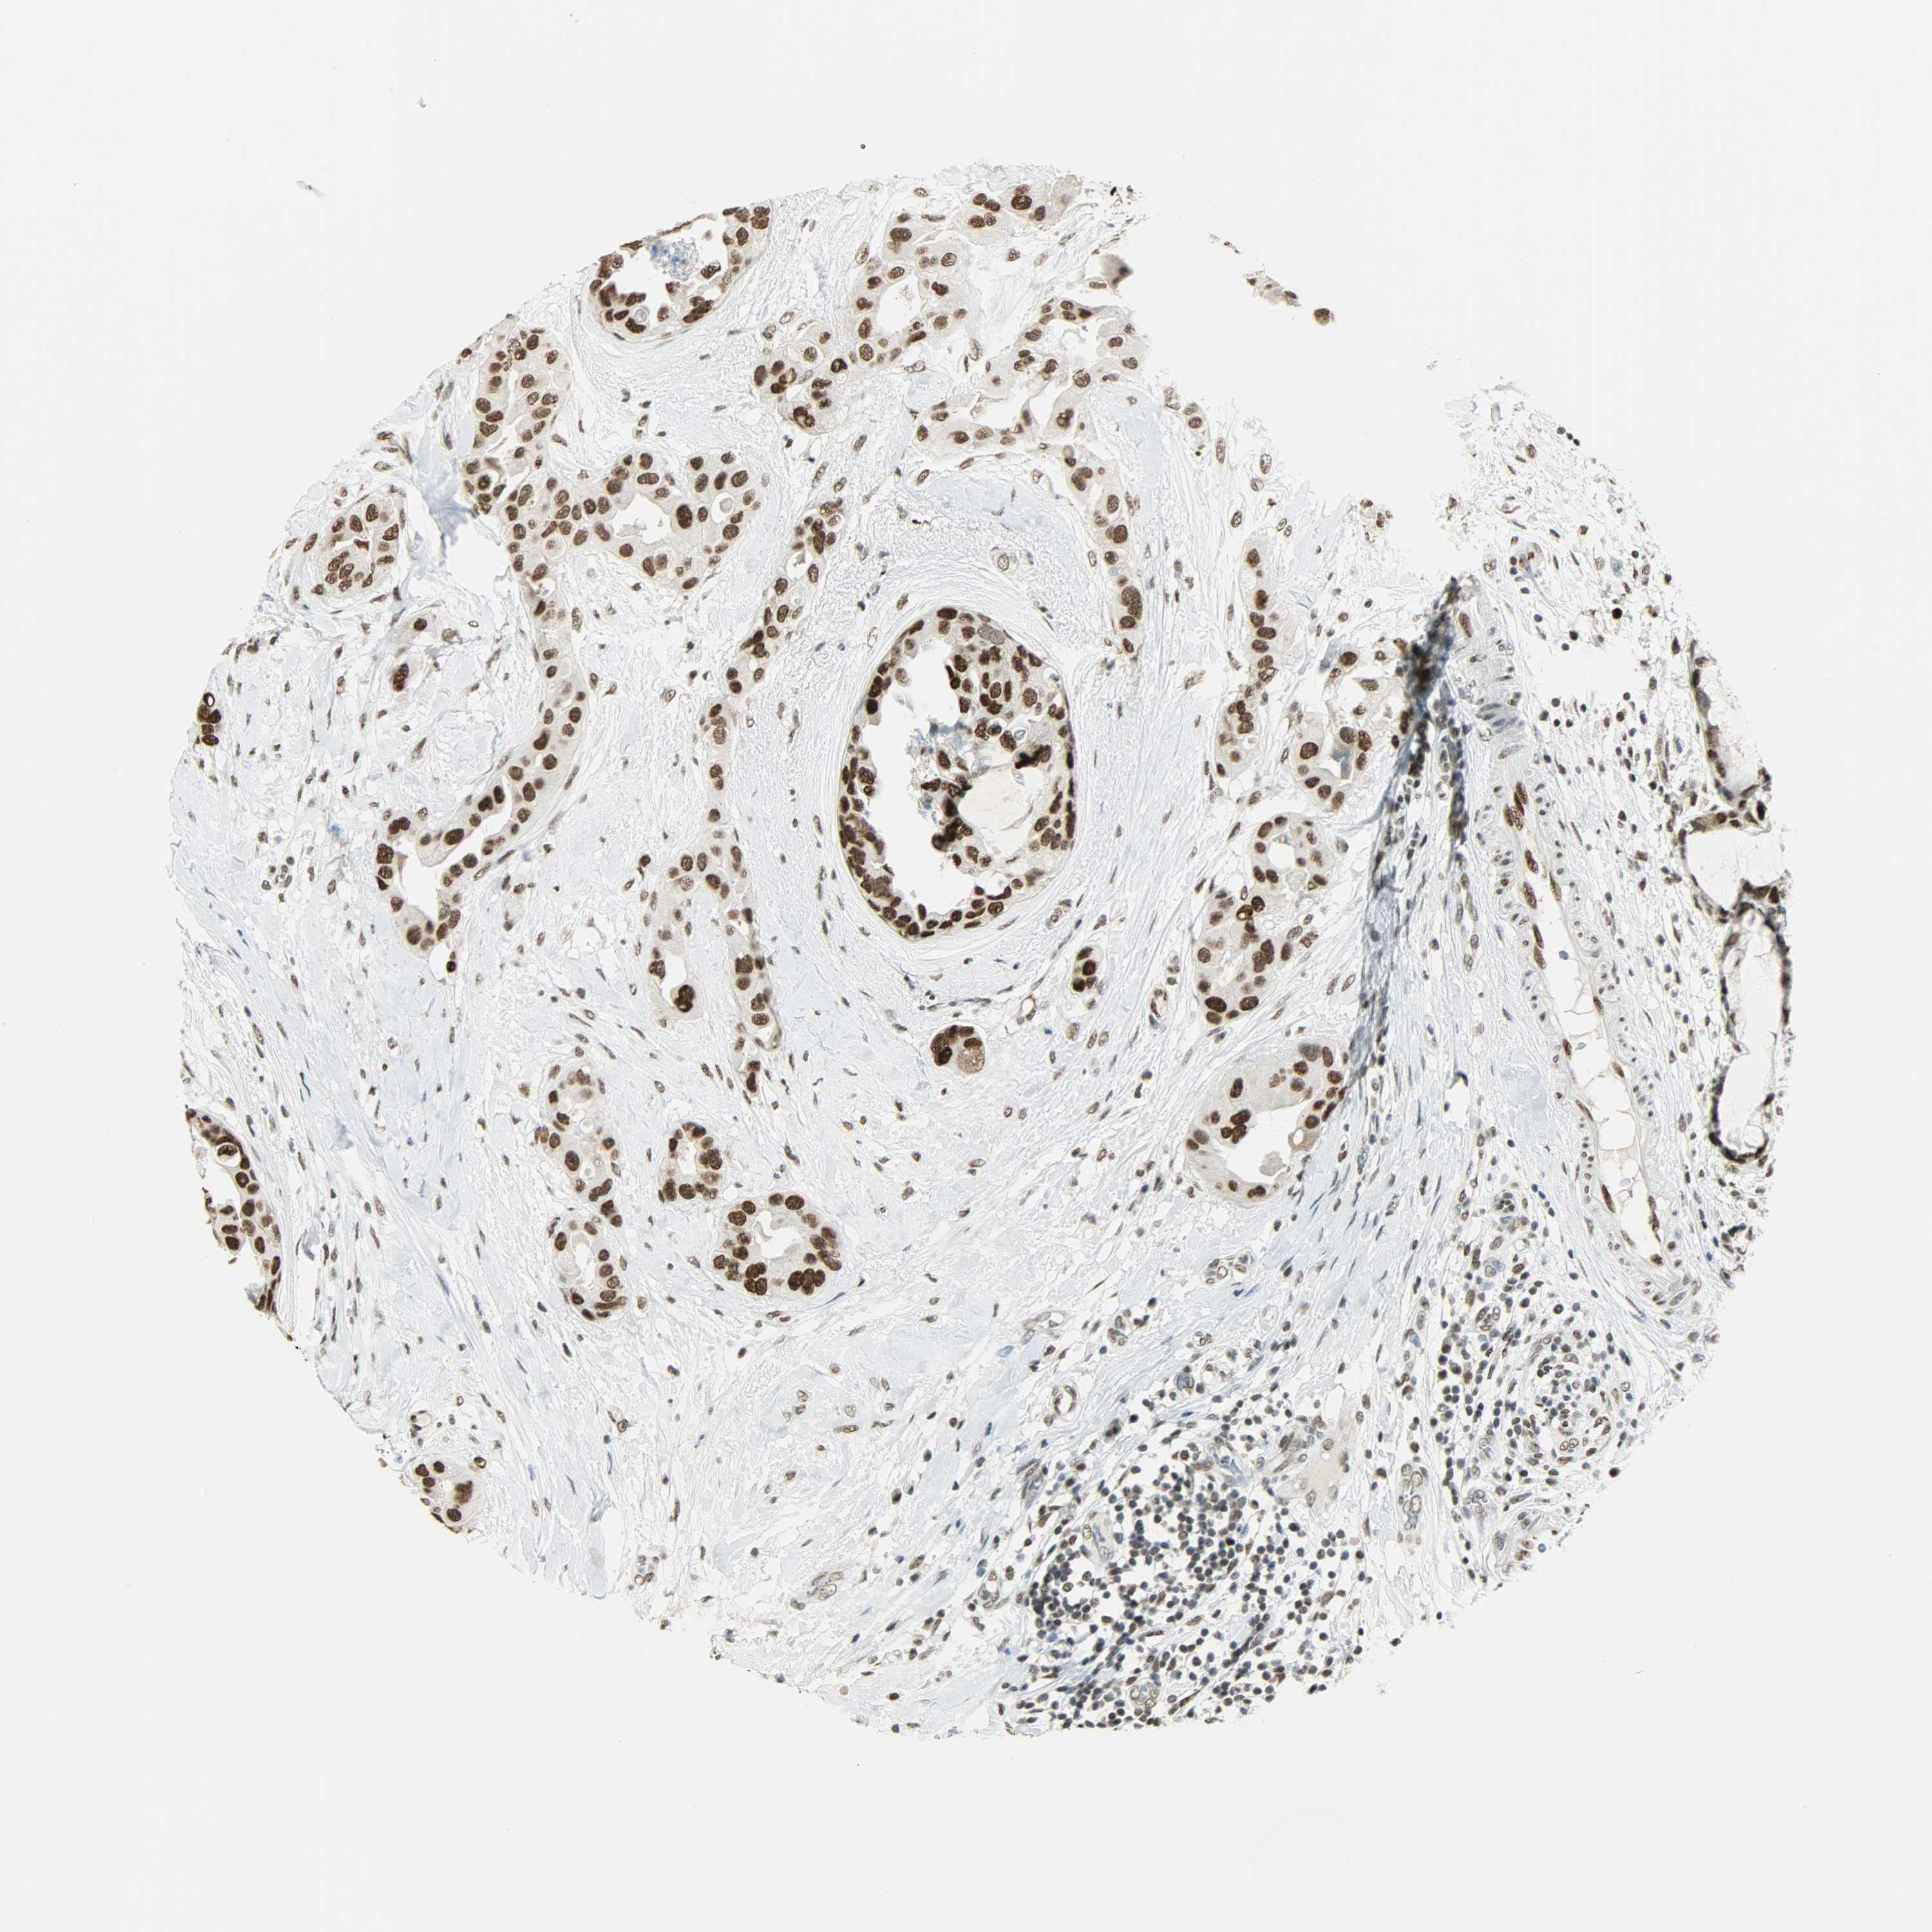

CANCER BREAST CANCER Show tissue menu

BRCA TCGA BRCA VALIDATION PROTEIN EXPRESSION